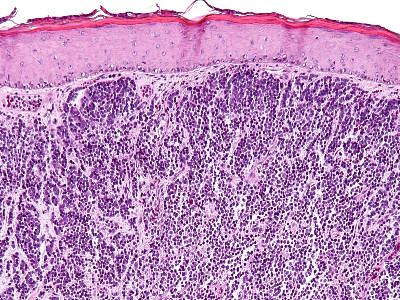

PA:

In de dermis, soms reikend tot in subcutis zijn velden van kleine ronde tumorcellen te zien (‘small blue round cells’). De tumorcellen zijn meestal gerangschikt in nesten, platen of strengen (trabekels). Soms worden ‘Homer-Wright pseudo-rosetten’ gezien, dat zijn kransen van tumorcellen rond een centrale zone gevuld met neurofibrillair materiaal, typerend voor neuro-endocriene tumoren. De tumorcellen zijn klein tot middelgroot en hebben zeer weinig cytoplasma en grote kernen t.o.v. de hoeveelheid cytoplasma. De celkernen vertonen een karakteristiek ‘salt and pepper’ chromatinepatroon (fijnkorrelig chromatine) met onopvallende nucleoli. Er zijn vele mitosen te zien. De tumor kleurt aan met cytokeratine 20 (CK20) en met neuro-endocriene markers (chromogranine A, synaptofysine, CD56). TTF (positief bij longcarcinoom) en S100 (positief bij melanoom) zijn negatief. Bij ongeveer 80% van de gevallen kan het Merkelcel-polyomavirus in de tumorcellen worden aangetoond.